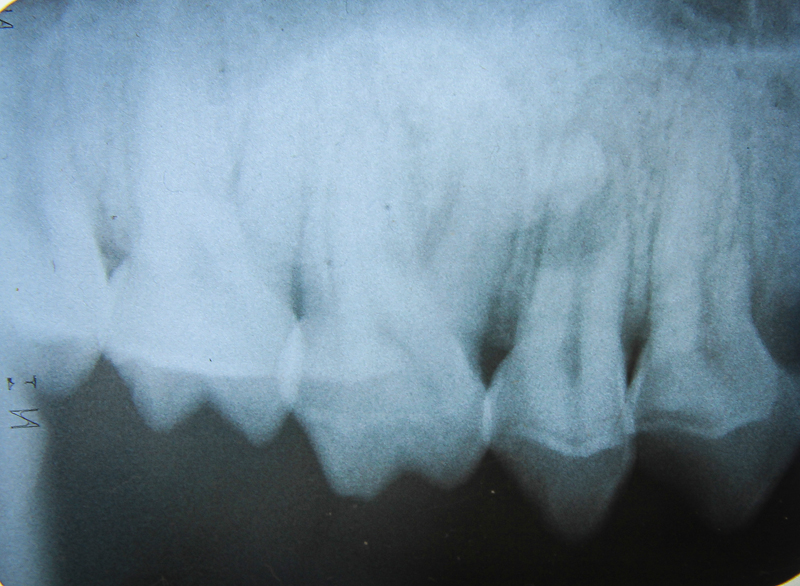

Preoperative radiograph. Note large diameter canine root canal in this young animal

Working length radiograph, 40 mm

Endo fill radiograph